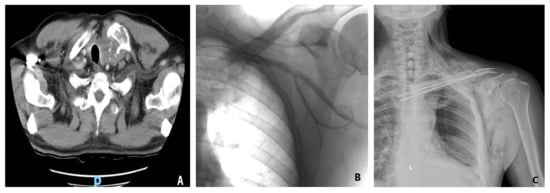

Figure 3.

Intraoperative aspect of a 64-year-old patient diagnosed with a manubrial tumor. A Gigli wire saw (A) was used for en bloc bilateral resection of the medial third of the clavicles, the cartilaginous portion of the first rib, and the manubrium (B). (C) Polypropylene mesh and Kryptonite cementum were used for rigid anterior chest wall reconstruction. (D) A 3D-CT scan reconstruction at three months after surgery shows the neo-sternum.

In the case of a primary chest wall tumor, a 4 to 5 cm tumor-free margin must be achieved, and the immediate adjacent ribs should also be resected [37,38]. For metastasis, the rule described by Leonardi requires a 2 cm parietectomy away from the tumor. Sternal manubrium tumors require resection of the internal third of the clavicles [39]. Reconstruction is not required following manubrial resection, en bloc or not, with either one or both clavicles [37,38]. In a case series of manubrial malignant tumors, reconstruction was successfully performed with autogenous rib grafts [40]. However, if the tumor affects at least 3 or 4 ribs, a paradoxical rib cage might occur, preventing complete re-expansion of the contralateral lung after surgery [37,38,41,42,43,44,45].